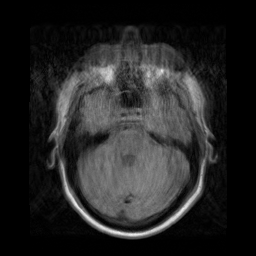

Motion artifacts are a primary source of magnetic resonance (MR) image quality deterioration with strong repercussions on diagnostic performance. Currently, MR motion correction is carried out either prospectively, with the help of motion tracking systems, or retrospectively by mainly utilizing computationally expensive iterative algorithms. In this paper, we utilize a novel adversarial framework, titled MedGAN, for the joint retrospective correction of rigid and non-rigid motion artifacts in different body regions and without the need for a reference image. MedGAN utilizes a unique combination of non-adversarial losses and a novel generator architecture to capture the textures and fine-detailed structures of the desired artifacts-free MR images. Quantitative and qualitative comparisons with other adversarial techniques have illustrated the proposed model's superior performance.

翻译:移动文物是磁共振(MR)图像质量恶化的一个主要来源,对诊断性能产生强烈影响。目前,MR运动的校正要么是预期性的,借助运动跟踪系统,要么是追溯性的,主要是利用成本昂贵的计算迭代算法。在本文中,我们使用名为MedGAN的新颖的对抗性框架,联合追溯性地校正不同身体区域的硬性和非硬性运动文物,而不需要参考图像。 MedGAN利用非对抗性损失和新型生成器结构的独特组合来捕捉无MR图象的纹理和精细详细结构。 与其他对抗性技术的定量和定性比较展示了拟议模型的优异性表现。